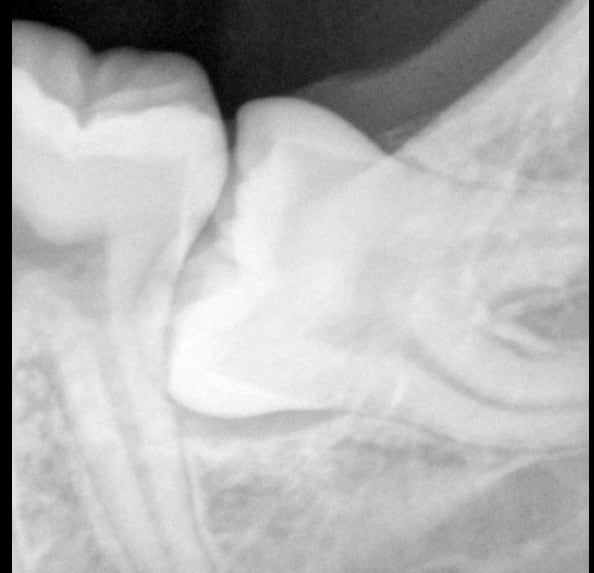

pour extraction de 48.

Effectivement les apex dépassent le bord inf. de la mandibule.

Merci. Je l'ai adressée hier au service de chirurgie maxillo-faciale universitaire de Bâle.C'est plus proche pour la patiente.Il y a non seulement un risque de fracture mais également un risque de lésion du NAI.Il faudra aussi faire une histologie de la lésion "Kystique".Je précise par ailleur qu'il n'y a aucune symptomatologie et 47 est vivante.

ca doit etre un kyste dentigere